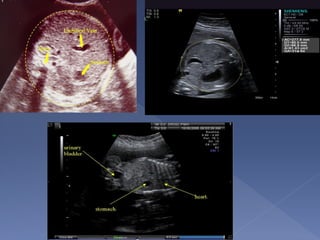

 Appropriate plane

› U/S beam should be perpendicular to the bone

› Measurement is made along the femur diaphysis

› Exclude the distal femoral diaphysis

Landmarks:

o Spine + rib

o Stomach

o Part of portal

vein

o Picture should

be as round as

possible

 The single most important measurement

to make in late pregnancy

 It reflects more of fetal size and weight

rather than age.

 Serial measurements are useful in

monitoring growth of the fetus.

 AC measurements should not be used

for dating a fetus.

 It is also a mandatory measurement.

Plane

 The best plane is the one in which the portal

vein is visualized in a tangential section.

 The plane in which the stomach is visualized

is also acceptable.

 The outer edge of the circumference is

measured

 On screen computer-generated elliptical

measurements probably yield the best

results